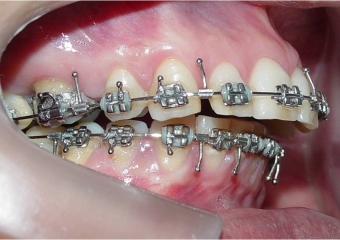

Mordida inicial